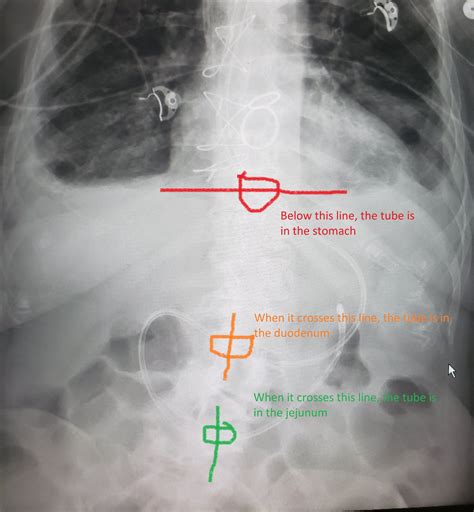

Diagnostic Imaging and the Ligament of Treitz

Radiologists rely on the Ligament of Treitz when interpreting imaging studies such as CT scans or fluoroscopy (barium swallow/meal). The position of the duodenojejunal flexure in relation to the vertebral column and the midline can provide diagnostic clues for anatomical anomalies. For instance, in a normal anatomical presentation, the flexure should be to the left of the midline and at the level of the L1 or L2 vertebrae.

• ligament of treitz fluoroscopy

• ligament of treitz x ray

• ligament of treitz radiology